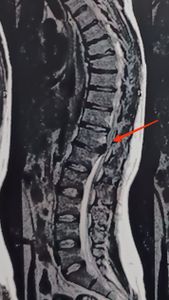

Meu nome é Marcos Vinicius Gomes eu sou Personal trainer e sofri uma lesão entre as vértebras T12 e L1 onde o disco está pressionando a minha medula.

Causando não só dores mas a perda de força na perna e futuramente paralisia além de perca da função baixa do intestino e bexiga caso eu não opere.